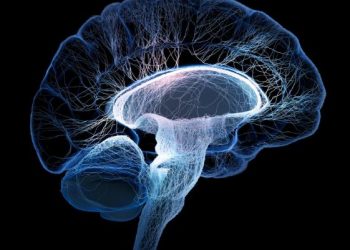

يمثل سرطان الدماغ ما يقرب من واحد من كل مائة تشخيص بالسرطان كل عام في الولايات المتحدة. غالبًا ما تنتشر...

يعد سرطان الدماغ من أكثر أنواع السرطانات فتكًا. من بين جميع أنواع السرطان ، فهو الأكثر تشخيصًا ، مع ما...

قد يكون تشخيص سرطان الدماغ أمرًا صعبًا لأن الأعراض غالبًا ما تحاكي الأعراض التي تسببها أمراض أخرى. يوجد في سرطان...